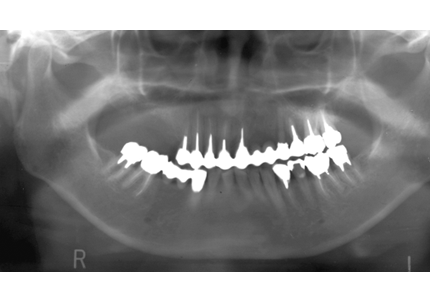

↑2006年4月24日

↑2008年12月

24.パノラマレントゲン

↑2006年4月24日(初診時)

↑2024年6月26日